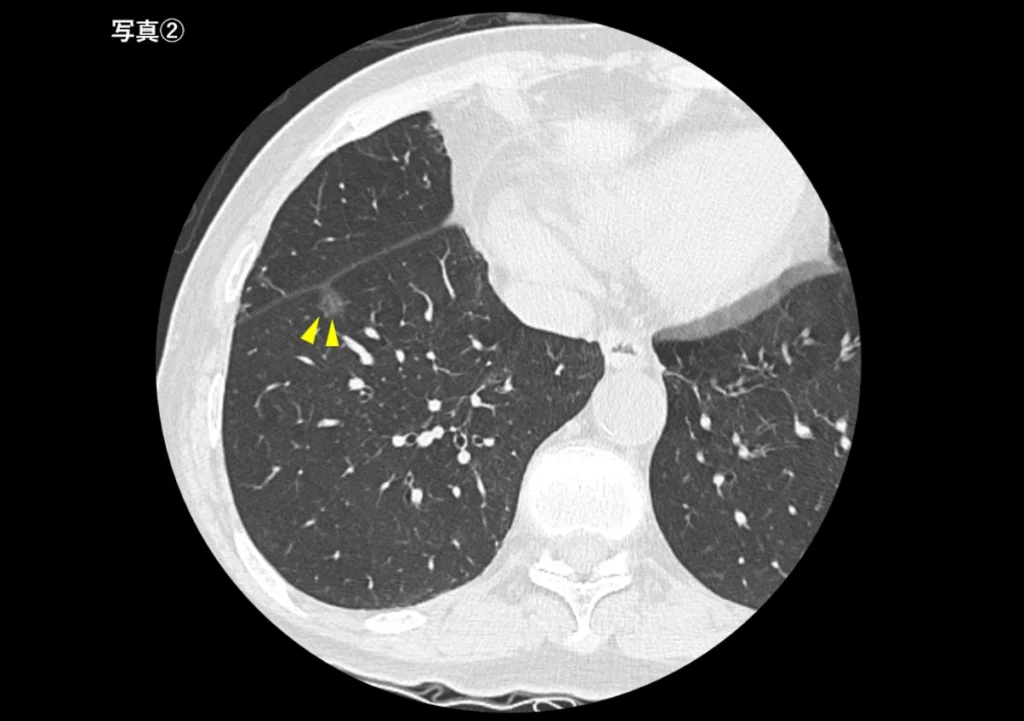

小さな肺がん(写真②)

数ミリ〜1cm程度の小さな腫瘍は、レントゲンでははっきり写らないことがあります。